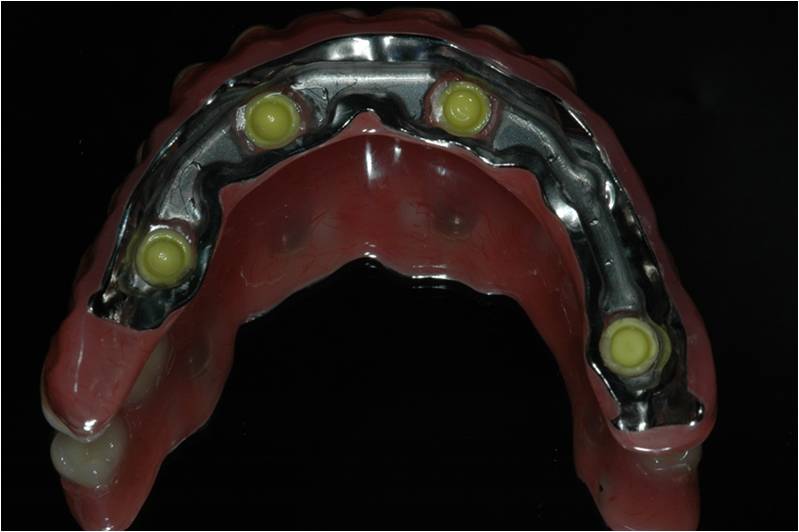

מקרה המתאר חוסר שיניים מוחלט בלסת עליונה.

סוג השיקום הוא " קבוע נשלף" FIXED DETACHABLE.

זהו שיקום המתפקד כמו גשר קבוע יציב לחלוטין אך ניתן להסרה וניקוי בצורה יעילה כפי ששום שיקום אחר אינו מאפשר.